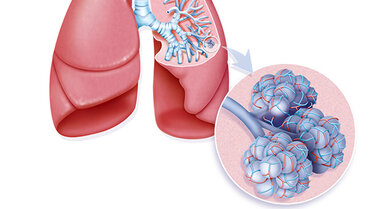

Sie sind der Ort, an dem die Lunge ihre wichtigste Funktion, den Gasaustausch wahrnimmt und geben dem Lungengewebe sein schwammartiges Aussehen.

Der rechte Lungenflügel hat drei Lappen, der linke zwei. In den Lungenbläschen (vergrößerter Ausschnitt) findet der Gasaustausch statt

© Your Photo Today/A1Pix